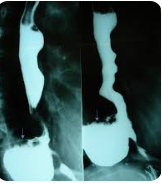

Figura 2: Comparação entre contraste hidrossolúvel (esquerda) e sulfato de bário (direita)

Contraste hidrossolúvel vs sulfato de bário